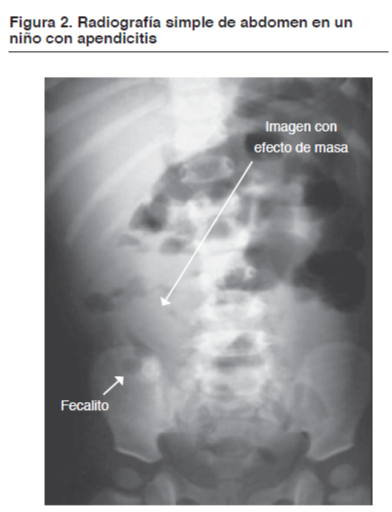

- Estudios por imagenes